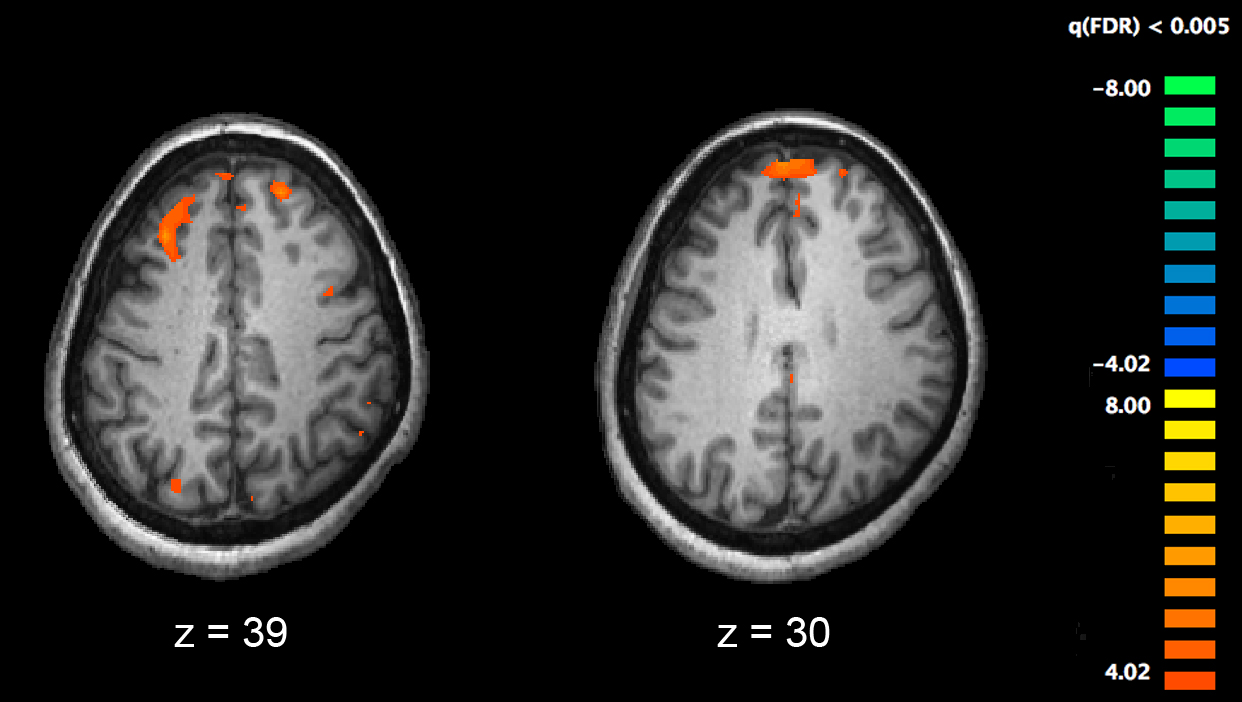

这幅图像显示了大脑的两个层面,健康对照组的大脑区域比精神分裂症患者更活跃(橙色显示)。

在这项研究中,来自世界各地的40多名科学家,对1717名包括健康人和精神分裂症患者在内的志愿者的大脑核磁共振扫描和认知功能进行了分析,由此产生了一种新的方法来协调数据收集和分析,相关结果成为“通过荟萃分析项目加强神经影像遗传学(ENIGMA)”工作的一部分。

之前的文献表明,一般认知功能依赖于大脑的特定灰质区域,包括颞区、顶叶区和额叶区。然而,这项研究的结果表明,整个大脑的有效连接通路提供了支持一般认知功能的神经网络。